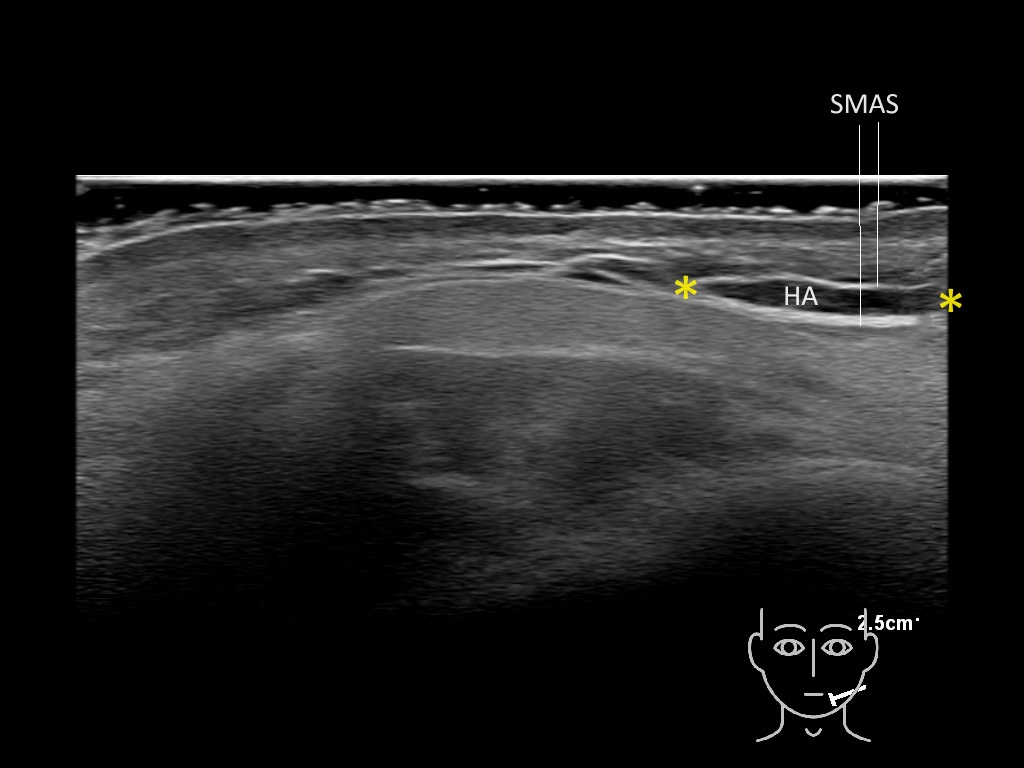

Filler deposits may end up unintentionally in the SMAS or fascial layers of the skin. Very often this will not lead to adverse events, however, adverse events ( nodules, migration / redistribution impaired muscle movement and smiling and malar edema) are are often related to filler ending up in the SMAS or fascia.

Study the first image to recognize the different layers. If you are sure about the layers, swipe to the second image to view the answer (if applicable).